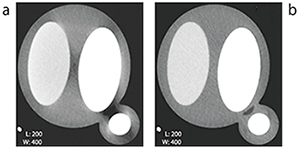

図8 従来(a)とMMAR(b)の比較